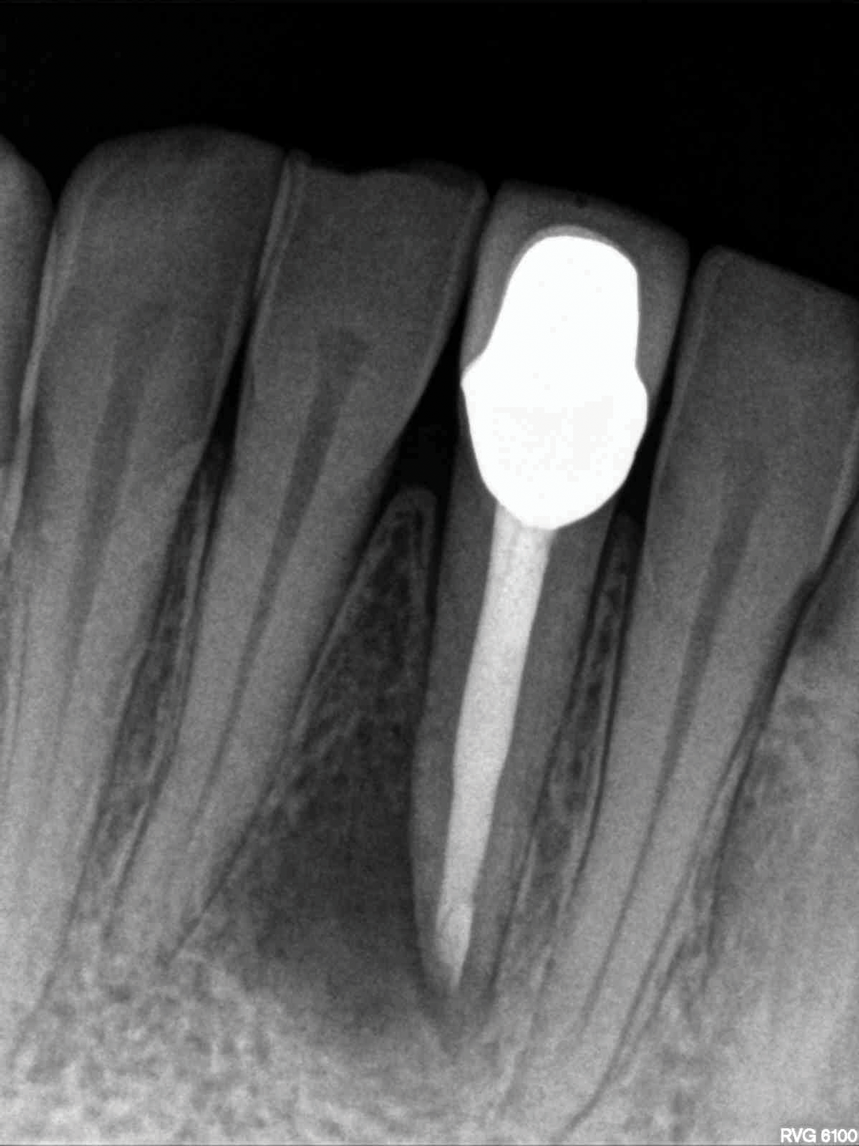

Fig 1. NSRCT can have high success, even with risk factors like periapical pathology associated, as depicted in this case presentation. Fig 1: Preoperative periapical radiograph showing AP. Fig 2: Preoperative CBCT. Fig 3: Immediate postoperative periapical radiograph. Fig 4: Three-month follow-up CBCT showing reduction of periapical radiolucency. Fig 5: One-year follow-up periapical radiograph showing resolution of periapical radiolucency.

Figure 1

Fig 1 through Fig 5. NSRCT can have high success, even with risk factors like periapical pathology associated, as depicted in this case presentation. Fig 1: Preoperative periapical radiograph showing AP. Fig 2: Preoperative CBCT. Fig 3: Immediate postoperative periapical radiograph. Fig 4: Three-month follow-up CBCT showing reduction of periapical radiolucency. Fig 5: One-year follow-up periapical radiograph showing resolution of periapical radiolucency.

Just as systemic conditions and patient habits impact outcomes after NSRCT, the local dental environment and dental disease states also impact outcomes (Figure 1 through Figure 5). In the Toronto study evaluating 4- to 6-year outcomes following NSRCT, the presence of a periapical radiolucency emerged as a key prognostic factor, substantially reducing the success rate by a factor of four.12 Single-rooted teeth experienced better outcomes compared to multirooted teeth in the presence of periapical lesions.1 Teeth diagnosed preoperatively with irreversible pulpitis or necrosis, in the absence of AP, showed a more favorable prognosis compared to those with preoperative AP.2